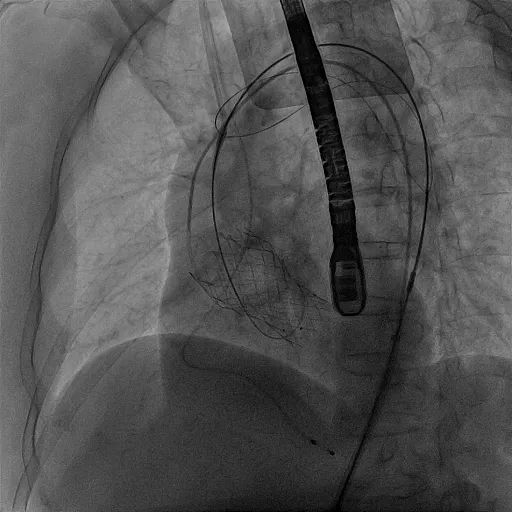

手术开始后,使用猪尾导管在无名动脉在造影辅助下选定TriGUARD3™锚定区,确认释放位置,经由左股动脉送入脑保护装置,使脑保护装置完全覆盖头臂动脉、左颈总动脉、左锁骨下动脉开口。

TriGUARD3™定位

TriGUARD3™完成释放